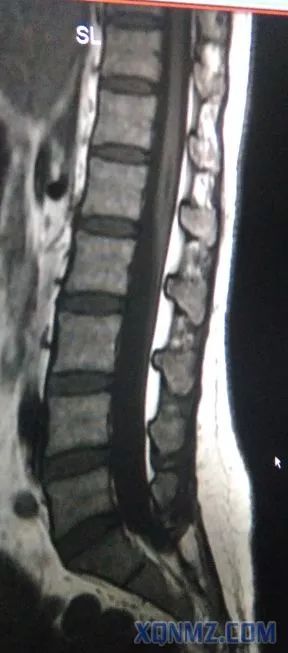

下面是我工作中在影像科学习时发现了一例中年女患,脊髓变异,终止于L3-4,而不是L1下缘,此患者要是做腰麻后果不堪设想,相信大家做腰麻时不可能所有的患者都术前做磁共振检查吧。